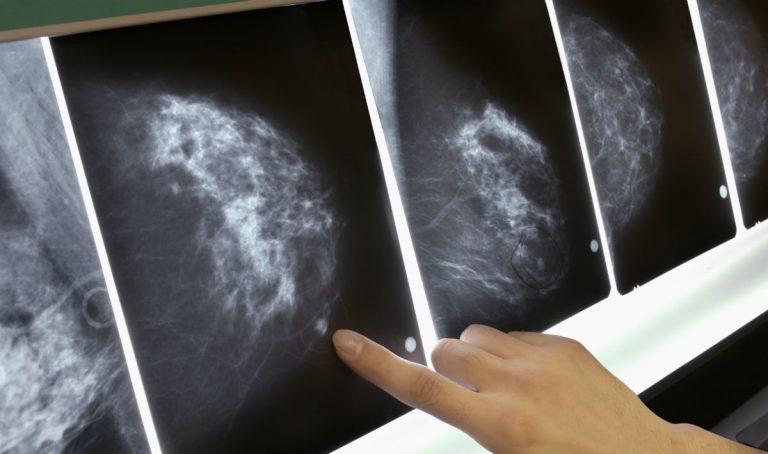

Tumore al seno - Foto GDS